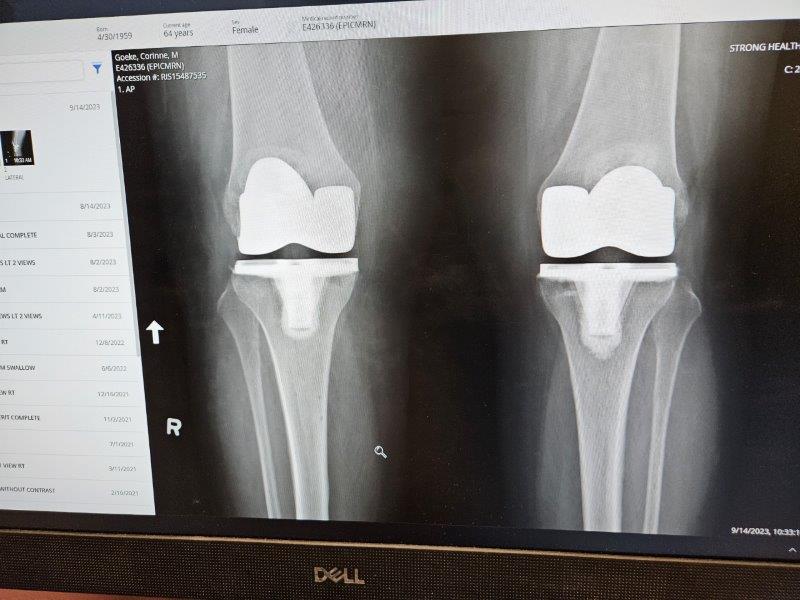

The second reason Alaska didn’t happen is my right knee. It had been getting progressively worse over time. If you recall, I had a full knee replacement on my left knee in February of 2021. Now it was time for the right knee. I really like the surgeon in Rochester who did the first knee. You know what is coming….road trip!

The first two weeks were a whirlwind of doctor’s appointments for both of us. Finally, on August 14th, I got my new knee.

After the surgery, the surgeon said it looked like a shark had taken a chunk out of my knee cap. Yes, it was that bad.

The next seven weeks were spent recuperating, going to physical therapy, and recuperating some more. Fortunately, this knee proved to be much more cooperative than the first knee, probably because the surrounding muscles weren’t as totally out-of-whack as they were with the first knee. Rehab happened three weeks quicker than I expected. Yay!